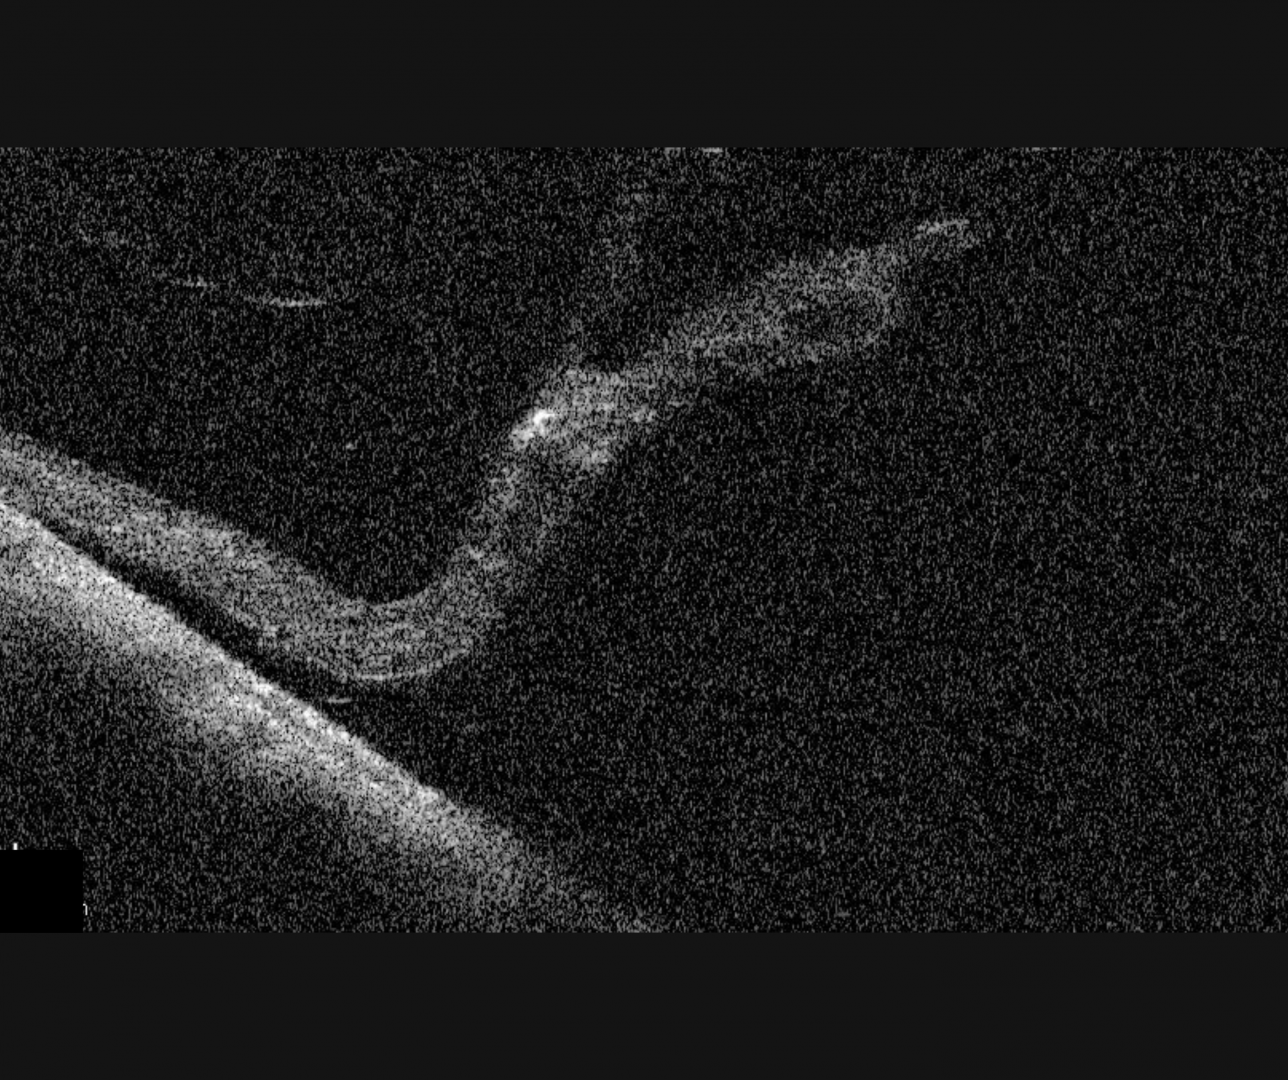

Peripheral OCT imaging can be used to confirm the separation of the photoreceptors from the RPE. The associated retinal break may be seen on OCT as a full thickness break. This initial break allows fluid the opportunity to enter the potential space between the neurosensory retina and the RPE, pushing the two layers apart. Chronic retinal detachments may be associated with retinal cyst formation and RPE hyperplasia.

More infoSpectralis OCT line scans through the area of chronic detachment (right eye)

More infoSpectralis OCT volume scan through the area of chronic detachment (right eye)